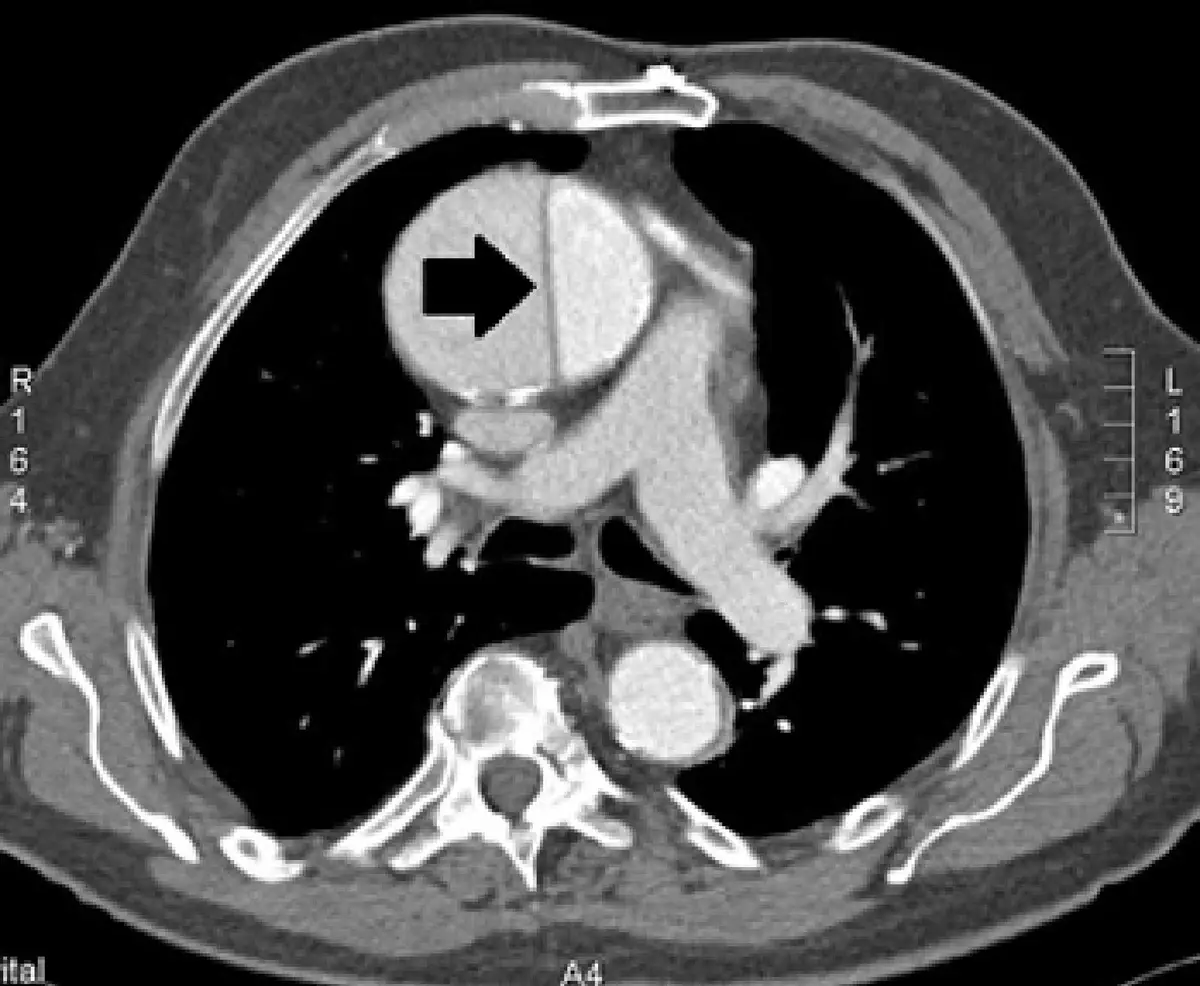

成人胸部電腦斷層影像如圖,造成箭號所指原因最可能為何?

- 箭號所指:黑色粗箭號指向升主動脈(ascending aorta)內部,可見一條線狀高密度隔膜結構,將主動脈管腔分隔為兩個腔室,形成「雙腔(double barrel)」外觀

- 線狀隔膜結構即為內膜瓣(intimal flap)——真腔與假腔之間的分隔

此影像特徵高度符合主動脈剝離的診斷:升主動脈內可見清晰的內膜瓣,管腔一分為二,為 Stanford A 型(累及升主動脈)主動脈剝離的典型 CT 表現。